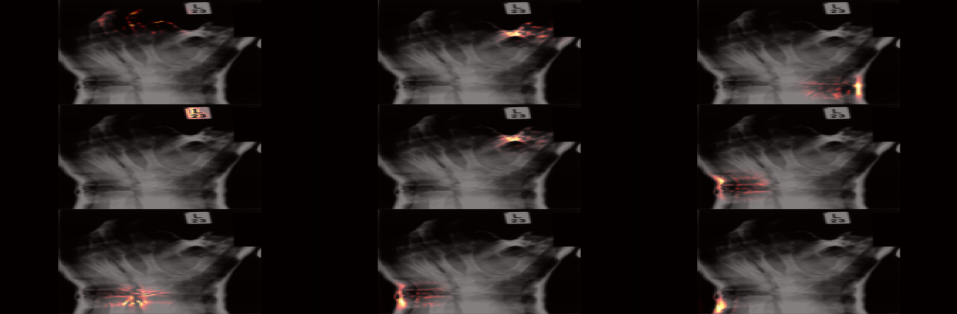

We visualized the internal activations of the models on test data through attentive response maps. More specifically, we combined the attentive response maps of the top = units from the last convolutional layer and overlayed them on the original image. In this way we constructed the focused attentive response maps that can be easily examined by a human expert. The = was chosen empirically as it produced attentive response maps closer to the anatomical landmarks with least number of units. The results are shown in 3, 4 and 5 for foot and hand classes from ImageClef dataset.

In Fig. 3 we show a correspondence between the obtained attentive response maps and the anatomical landmarks from the medical literature 222http://www.meddean.luc.edu/lumen/meded/radio/curriculum/bones/Strcture_Bone_teach_f.htm. Particularly for the foot image, we can observe that the edges of the metatarsals’ shaft has been used together with the distal phalangies, navicular, cuboid, tibia, and fibula. Similarly for the hand, three of the distal phalanxes, many of the heads of joints, metacarpals’ shafts as well certain carpals. In contrast to this, in Fig. 4 and Fig. 5 we can observe that the shallow and deep network trained without specific data augmentation fails to learn such specific landmarks. These models use broader ranges that are clearly not as specific as the information used in the first model. From the above visual results 333We obtained similar results for the other classes as well, but due to space constraints, only the results of two classes are shown. as well as the performance of the final model we come to the conclusion that sufficiently deep neural network models can be successfully trained to use the same medical landmarks as a human expert while attaining superior performance.